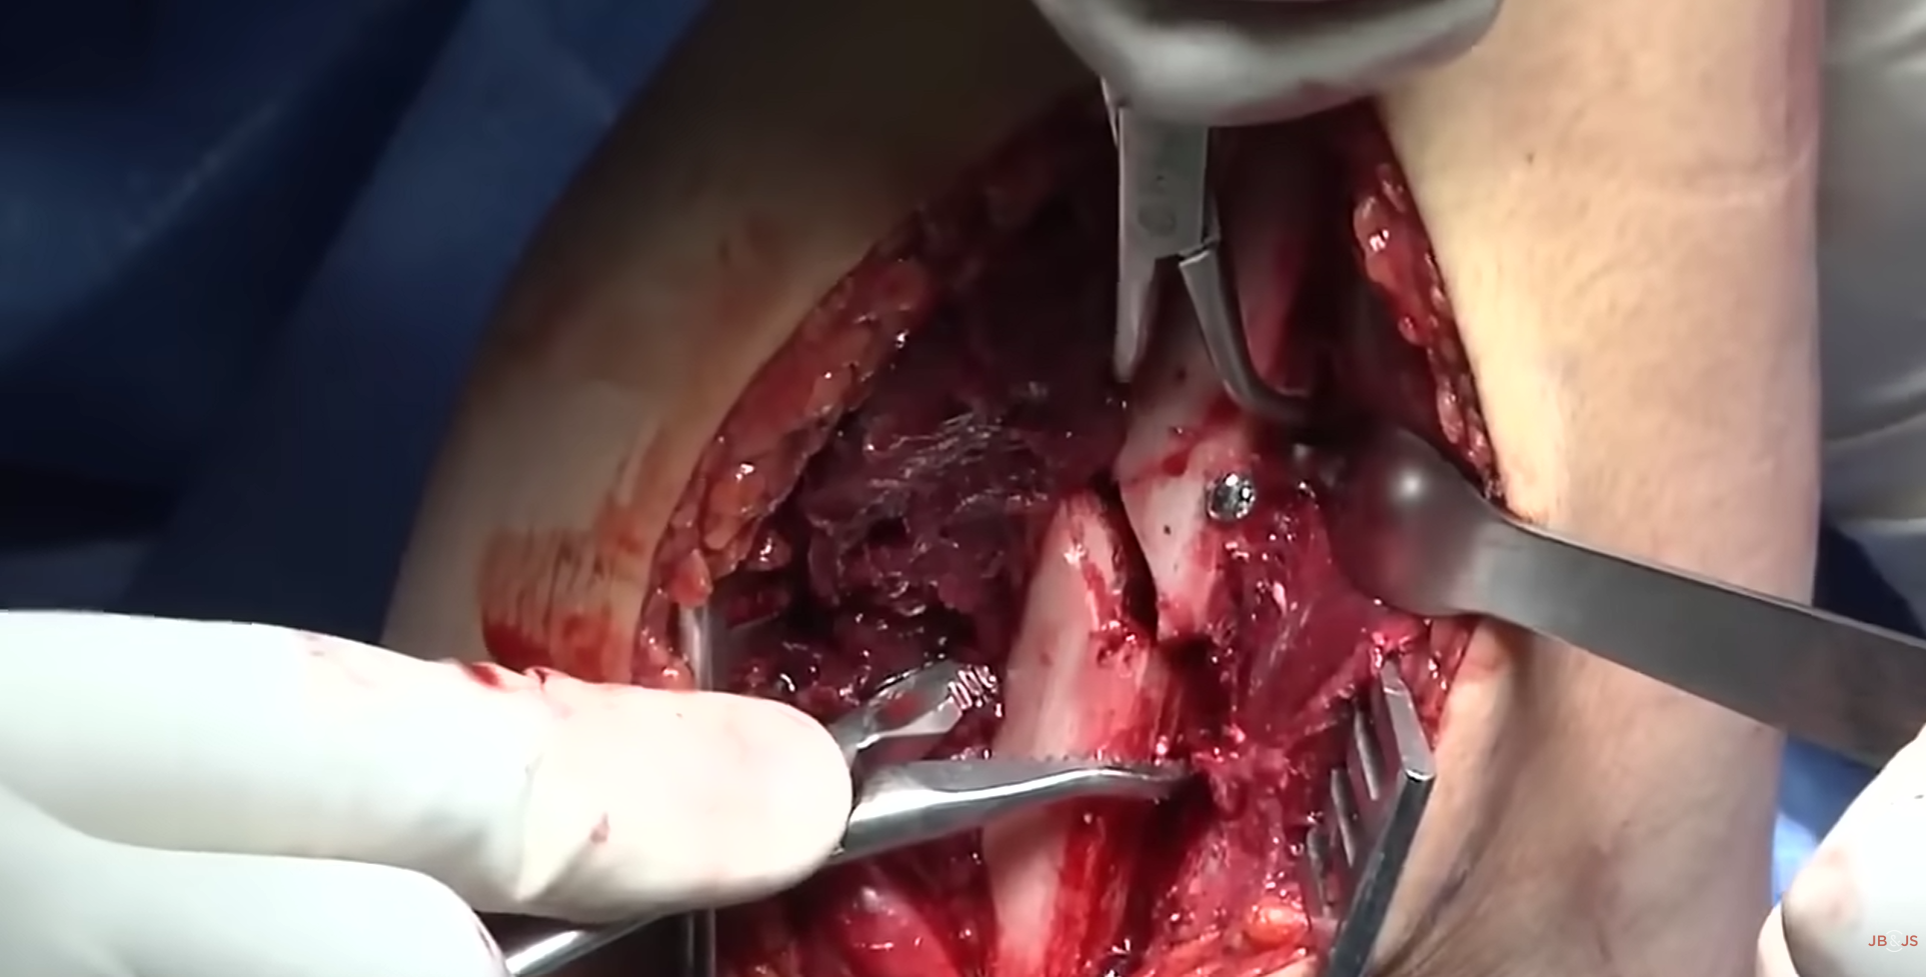

Cilt Grefti Uygulaması

Cilt Grefti Uygulaması

Cilt Grefti Uygulaması